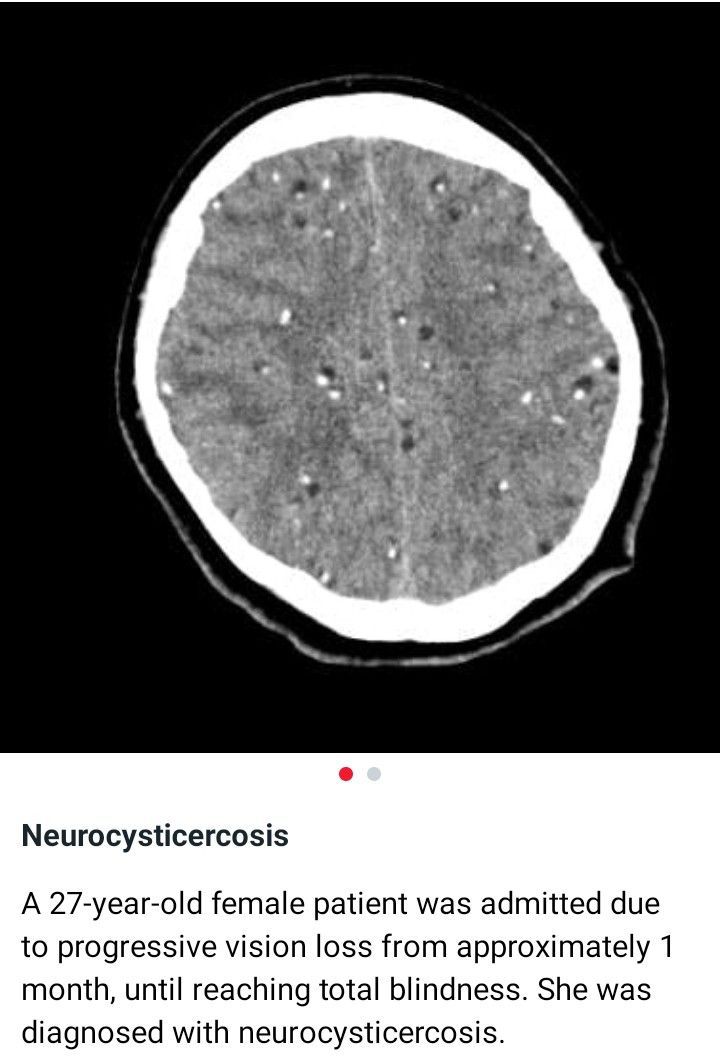

Neurosurgery

27